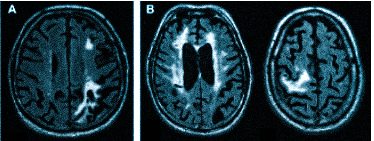

Что покажет МРТ при мигрени? Приступ мигрени сопровождается расширением сосудов мозга, за которым следует резкий спазм. МР-томограф фиксирует нарушения кровотока во время приступов и выявляет ишемические очаги, которые могут появляться в большом количестве.

При диагностике может быть назначено МРТ головного мозга для проверки сосудистых патологий. Мигрень возникает из-за временного сужения сосудов в мозге, что приводит к спазму. МРТ позволяет выявить нарушения кровотока и ишемические изменения.

- демиелинизацию при рассеянном склерозе и других атрофических процессах;

Если делать МРТ, когда не болит голова

Множественные ишемические очаги при сосудистой деменции на МРТ: отсутствие памяти на недавние события и неадекватное поведение не являются нормой для пожилых людей. Своевременная диагностика деменции и патогенетическая терапия могут замедлить прогрессирование болезни.